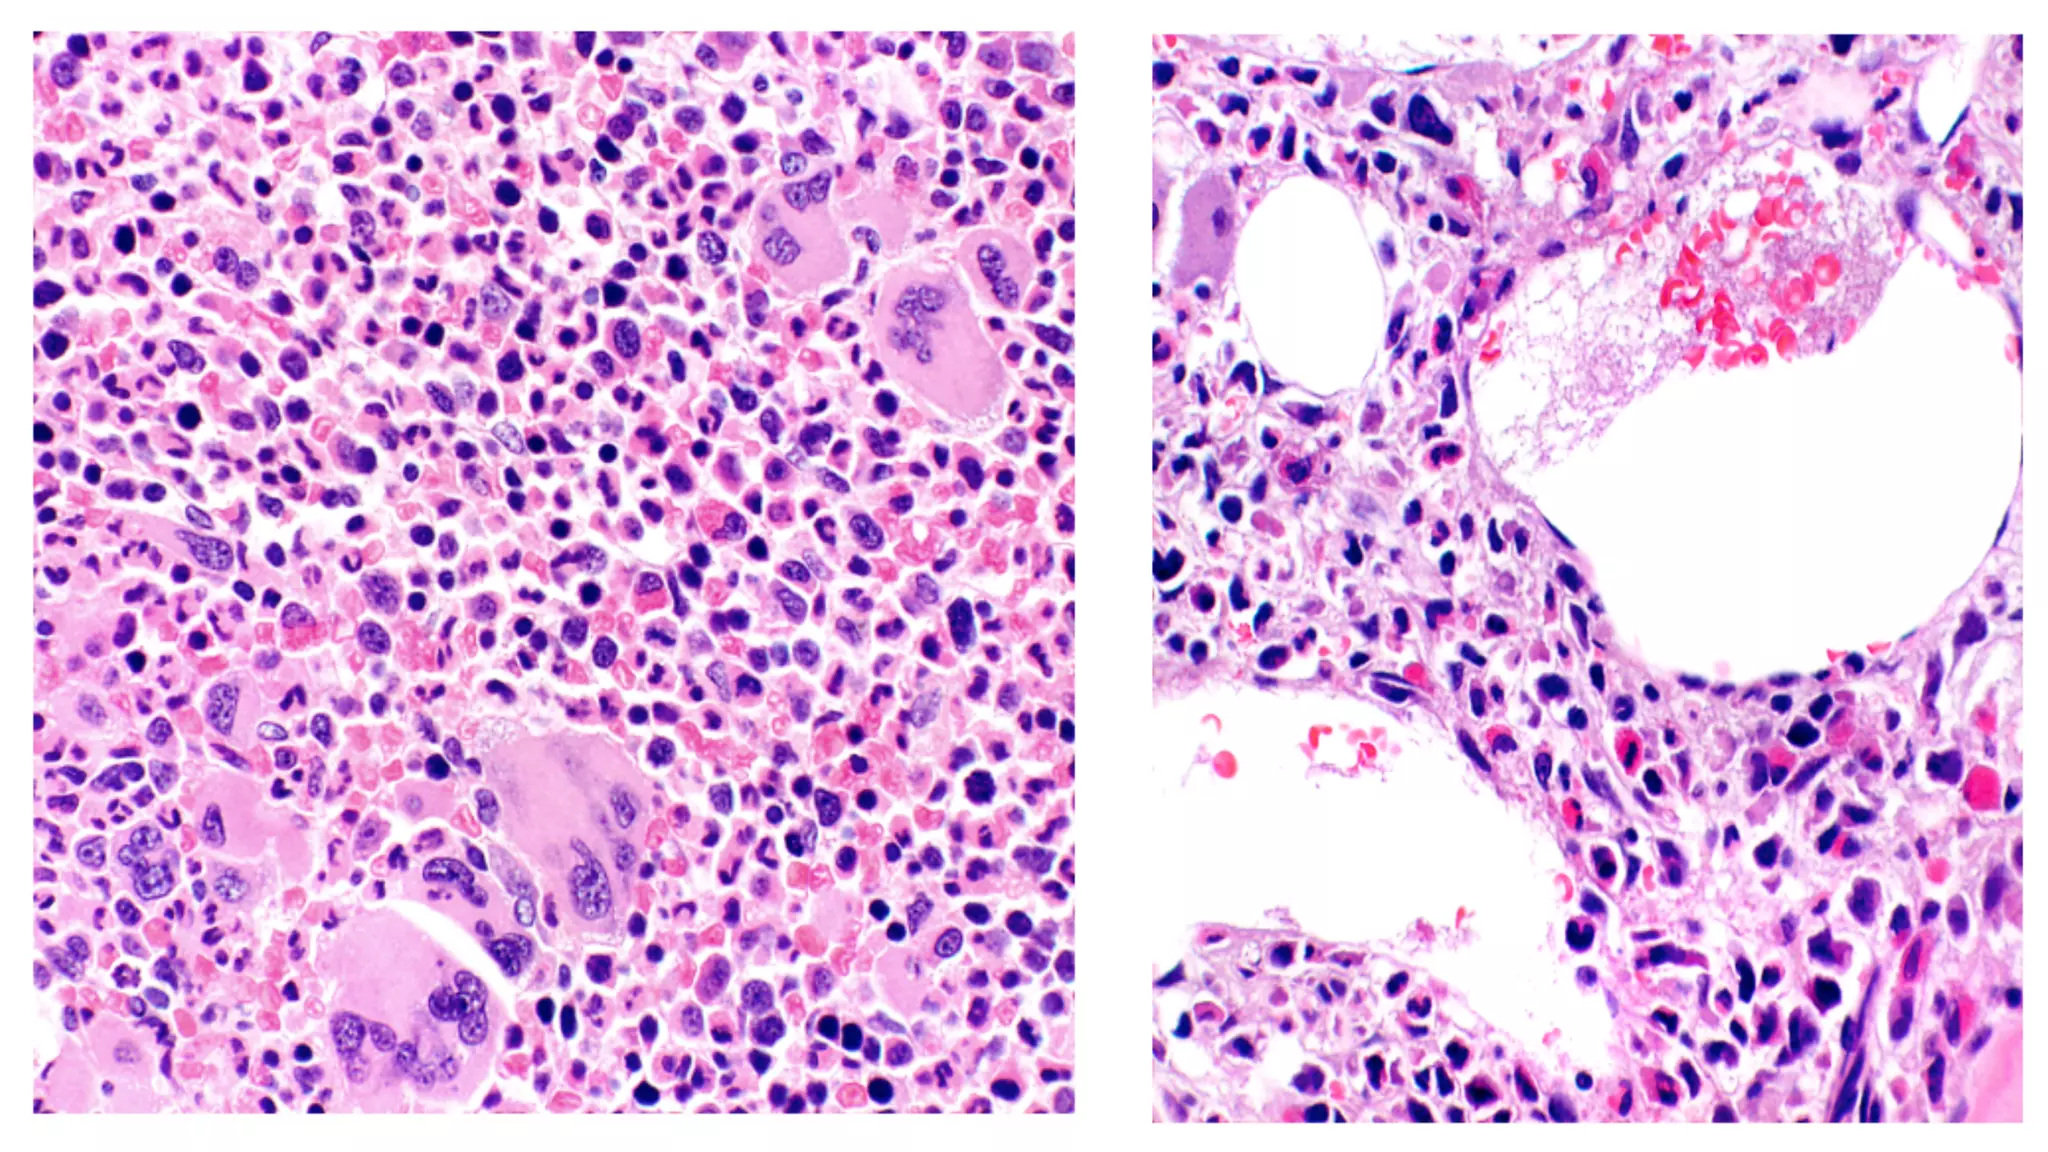

Megakaryocytes in ET Megakaryocytes in prePMF

Megakaryocytes in ETMegakaryocytes in prePMF